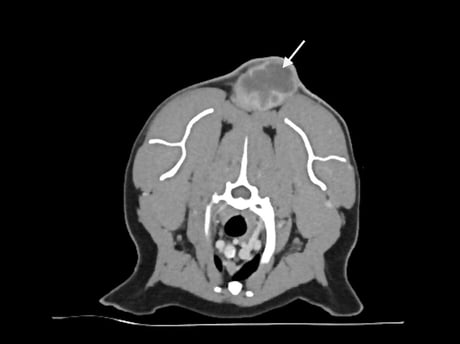

FISSs typically have long finger-like projections lateral and deep to the main mass and can also have smaller “satellite” nodules peripheral to the primary tumour. Contrast-enhanced computed tomography (CT), or less commonly MRI, helps visualise these and aid surgical planning (Figure 1). For interscapular ISS, post-contrast CT scans should be performed with the forelimbs extended both cranially and caudally along the body, as this allows a better understanding of the relationship between the tumour and adjacent tissue (Longo et al., 2018). As the surgical dose for ISSs can be large, imaging should include the abdominal and thoracic cavities to screen for comorbidities that may preclude a more invasive treatment approach.